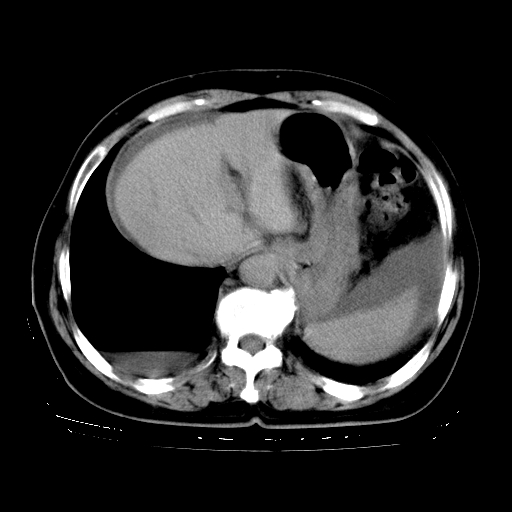

以下是引用zhangzhongshou在2008-3-22 12:52:00的发言:[br]1、右侧液气胸。[br]2、腹水。建议进一步检查。

以下是引用鲁巨ct在2008-3-22 14:10:00的发言:[br]1、右侧液气胸,右中下叶节段性不张。[br]2、腹水,建议上腹部ct检查

以下是引用zjzjr在2008-3-22 17:19:00的发言:[br]1、右侧液气胸,右下叶节段性不张。[br]2、腹水,建议上腹部ct检查